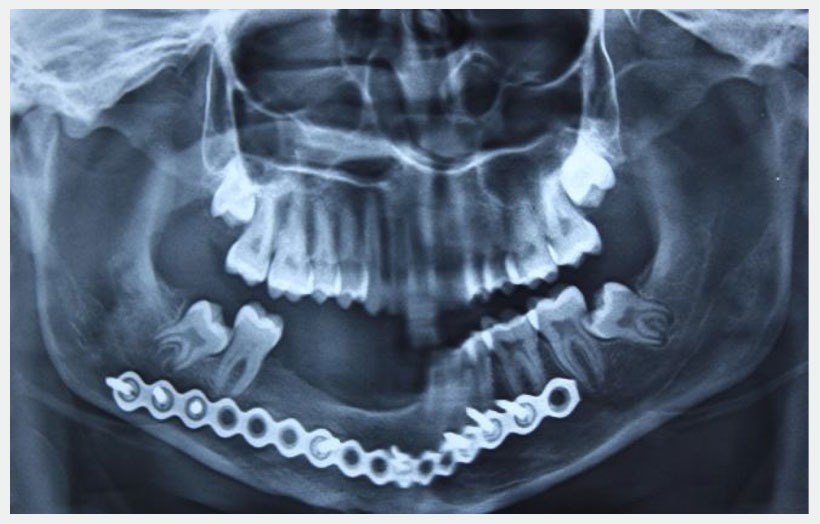

18 year old male patient came with chief complain of Swelling over Rt side of lower jaw. He was diagnosed as Benign Ossifying fibroma. Surgery was made in Feb 2013 for excision of lesion and reconstruction using Iliac crest cortico-cancellous bone graft from right side. Bone graft fixed to the defect using a reconstruction plate. After 1 year we can see adequate bone formation at the defect side. He is planed for replacement of missing teeth using 3 Alpha Dent 5×13 mm classic implants.